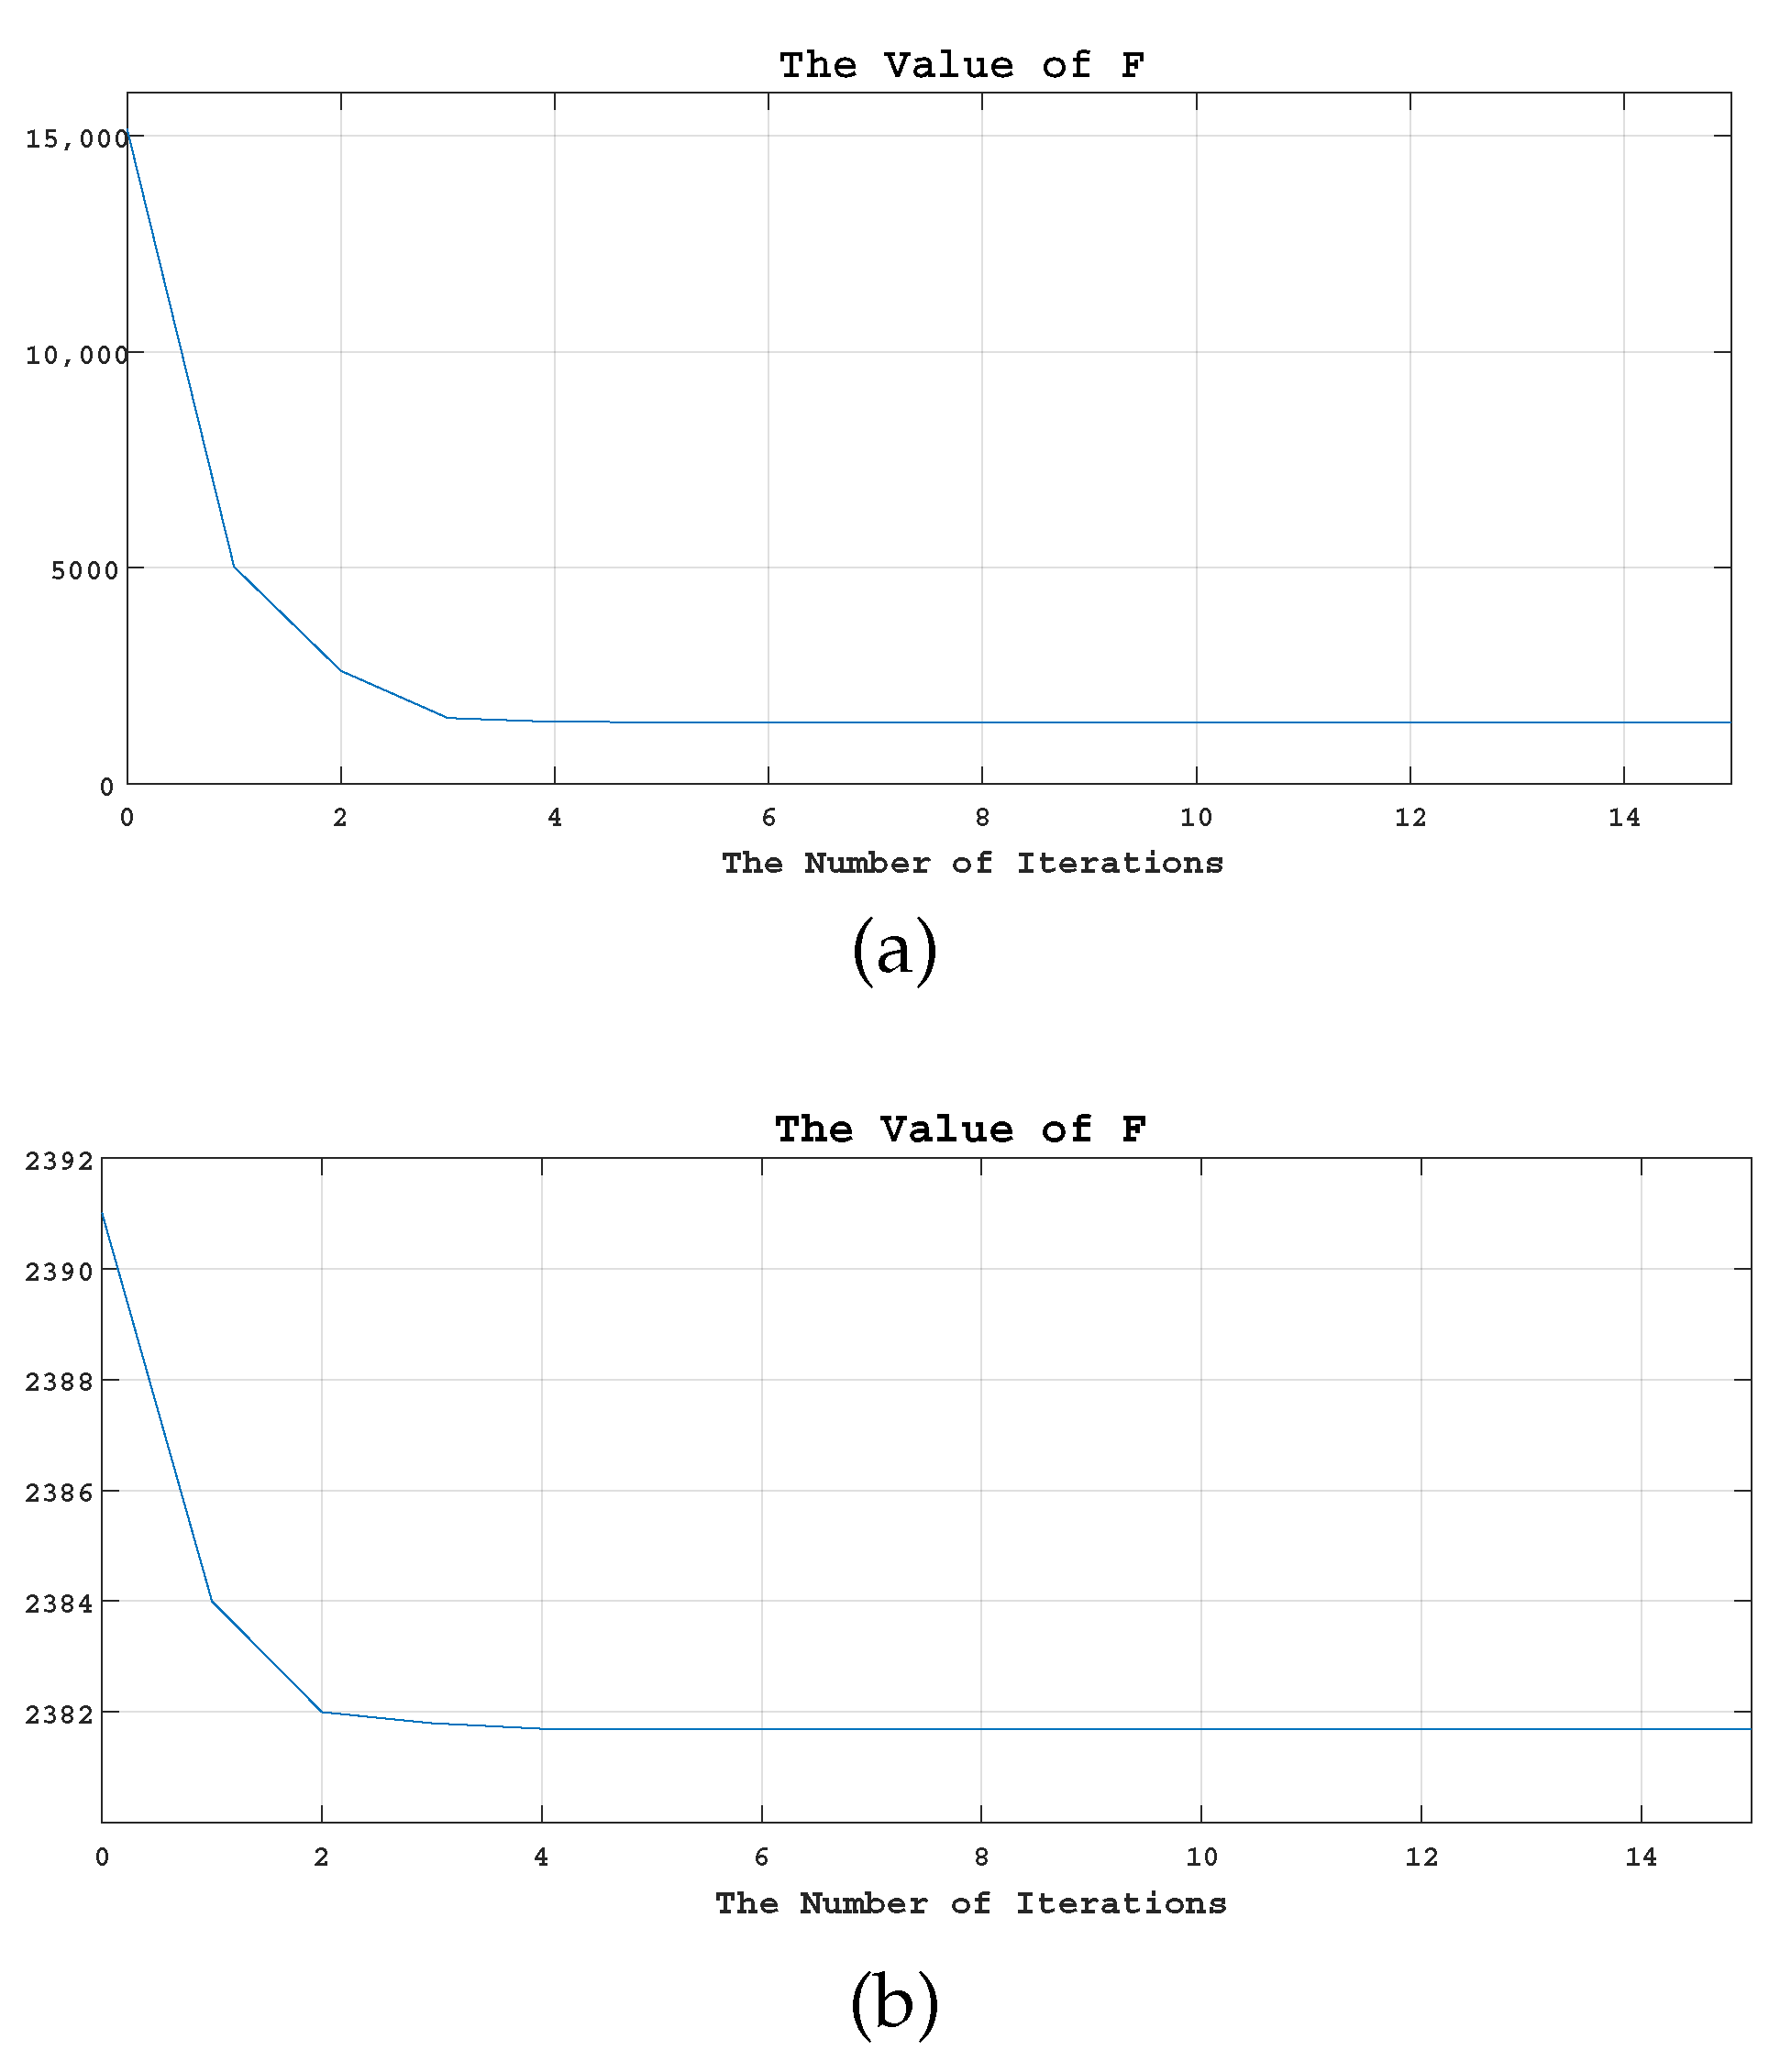

5.4.2. Convergence Analysis